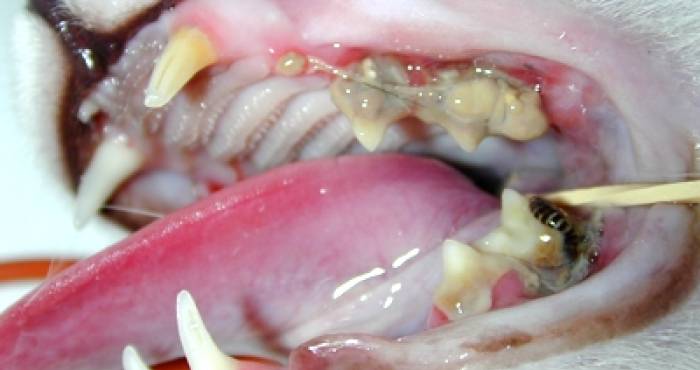

Os problemas dentários mais comuns nos cães e gatos são o acúmulo de cálculos bacterianos, ou as famosas placas bacterianas. Para se evitar isso, ou pelo menos tentar retardar o aparecimento delas, a escovação dentária é uma opção, mas o ideal mesmo é a remoção mecânica. “Essa remoção é feita com anestesia, e depois fazemos o polimento. Se não fizermos esse polimento, podem aparecer ranhuras mais tarde, e isso pode predispor ao aparecimento das placas cada vez mais cedo”, alerta a especialista.